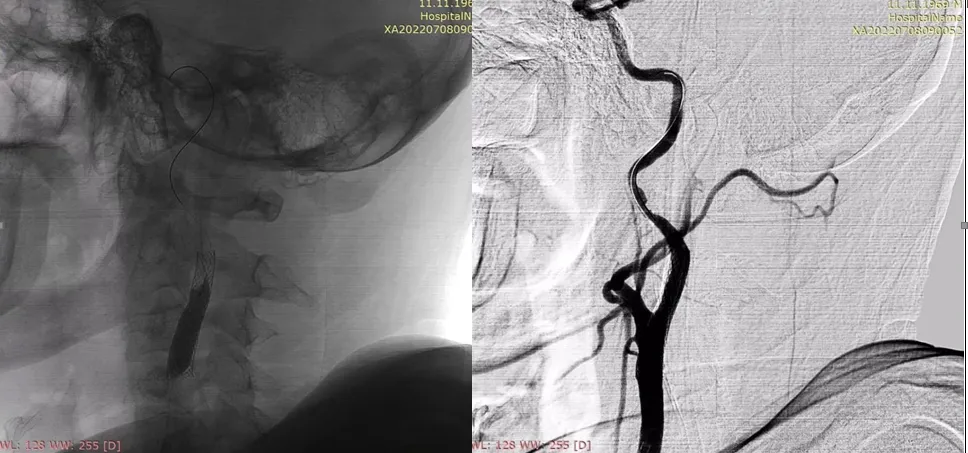

Для анестезіологічного забезпечення механічної тромбектомії застосовували седацію зі збереженням свідомості із забезпеченням кисневої підтримки через маску – 4 л/хв. АТ при ініціальному вимірюванні дорівнював 183/95 мм рт.ст. та не знижувався до моменту реперфузії басейну СМА. Час від початку захворювання до пункції стегнової артерії в ендоваскулярній операційній – 1255 хвилин. Оскільки дані МСКТ – ангіографії вказували на тандемну оклюзію (устя лівої ВСА та сегменту М1 лівої СМА) та демонстрували хорошу колатеральну компенсацію басейну лівої СМА, трансфеморальним доступом операційним провідниковим катетером відразу була проведена катетеризація лівої загальної сонної артерії без етапу діагностичної ангіографії. Цифрова субтракційна ангіографія дозволила з’ясувати місце відходження лівої ВСА від загальної сонної артерії та за допомогою балонного катетера для черезшкірної ангіопластики (percutaneous transluminal angioplasty balloon catheter) сформувати канал на рівні тромбованої атеросклеротичної бляшки ВСА (рис. 4) з метою проведення за межі оклюзії у дистальному напрямку операційного провідникового катетера.

Рисунок 4. Цифрова субтракційна ангіографія, лівий каротидний басейн, ліва косо- фронтальна проекція. Місце відходження лівої ВСА від загальної сонної артерії (червона стрілка). Наповнення балонного катетера на рівні тромбованої атеросклеротичної бляшки (балон позначено жовтою стрілкою).